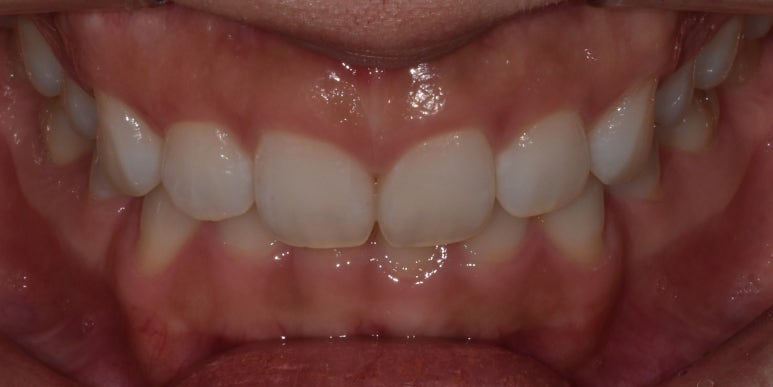

잇몸성형 시술 사례

(전) 2022-09-03 (후) 2022-09-16